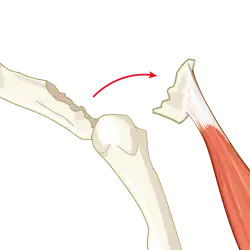

An avulsion fracture is a bone fracture which occurs when a fragment of bone tears away from the main mass of bone as a result of physical trauma. This can occur at the ligament by the application of forces external to the body (such as a fall or pull) or at the tendon by a muscular contraction that is stronger than the forces holding the bone together. Generally muscular avulsion is prevented by the neurological limitations placed on muscle contractions. Highly trained athletes can overcome this neurological inhibition of strength and produce a much greater force output capable of breaking or avulsing a bone.